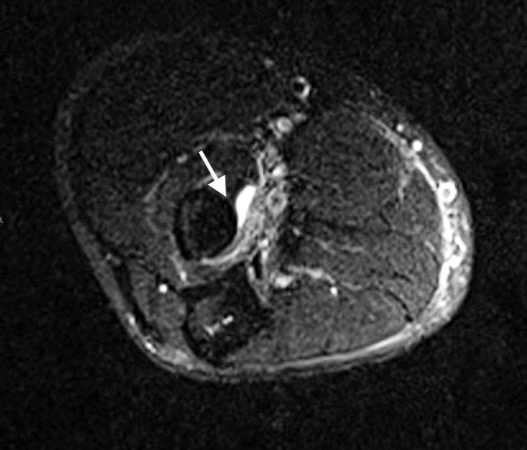

• 1.	This MRI (T2) cross-sectional image at the level of the elbow shows the radius and the insertion site of the biceps tendon on the radius tuberosity (arrow). The ruptured biceps tendon is not present. Edema (white) secondary to the biceps rupture is evident at the tuberosity.  The structures adjacent to the edema are the neurovascular bundle and surrounding fatty tissues.

1. This MRI (T2) cross-sectional image at the level of the elbow shows the radius and the insertion site of the biceps tendon on the radius tuberosity (arrow). The ruptured biceps tendon is not present. Edema (white) secondary to the biceps rupture is evident at the tuberosity. The structures adjacent to the edema are the neurovascular bundle and surrounding fatty tissues.